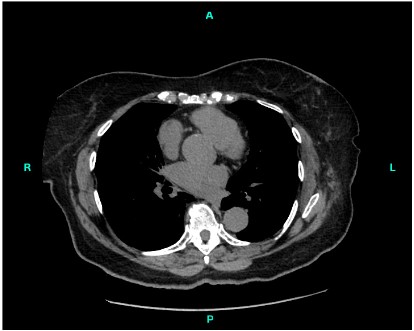

An 82-year-old female was found to have a growth located in the anterior lobe of the left lung, which was later identified as an angiomyolipoma (Figure 1). Clinical history of the patient revealed the growth to be a slow-growing left lower nodule.

Figure 1: An 82-year-old patient presents with growth eventually identified as extrarenal angiomyolipoma. Non-contrast axial multidetector CT scan of chest performed from lung apices to lung bases. High resolution images through upper, mid and lower chest. Images of patient taken approximately two months prior to VATS procedure. 1.5 x 1.4 cm well-defined soft tissue lesion left anterior lower lobe of lungs identified.